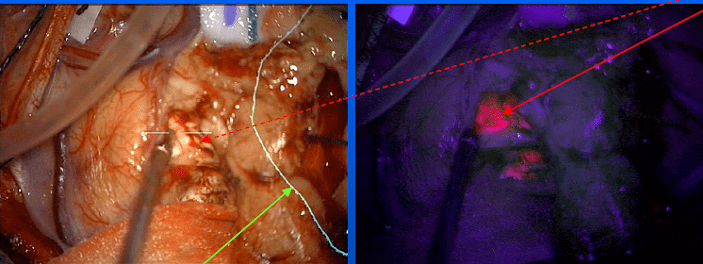

Andrew Sloan, MD, Director, Brain Tumor and Neuro-Oncology Center (BTNOC), Peter D. Cristal Chair of Neurosurgical Oncology, and Vice Chairman of Neurological Surgery, noted that new and innovative approaches to surgery often help improve the extent of resection in brain tumors. 5-Aminolevulinic acid (5-ALA) is given prior to surgery and makes the tumor fluoresce pink for more precise identification of its borders. A newer approach using cell-surface protein tyrosine phosphatase mu (Ptpu), funded by a grants to Dr. Sloan & collaborators by the Coulter Fund and the National Institute of Health (NIH), may be even more tumor specific.

Photo: Brain tumor under normal light (red arrow on left). 5-Aminolevulinic acid (5-ALA) makes the tumor fluoresce pink for more precise identification of its borders (red arrow on right)

“This is important because where the tumor ends and normal brain begins is not always obvious to the surgeon. Importantly, of the five prognostic indicators that determine survival for brain cancer, extent of resection is the only one that physicians can influence,” Dr. Sloan said. Leaving even a small amount of tumor behind greatly decreases a patient’s survival.